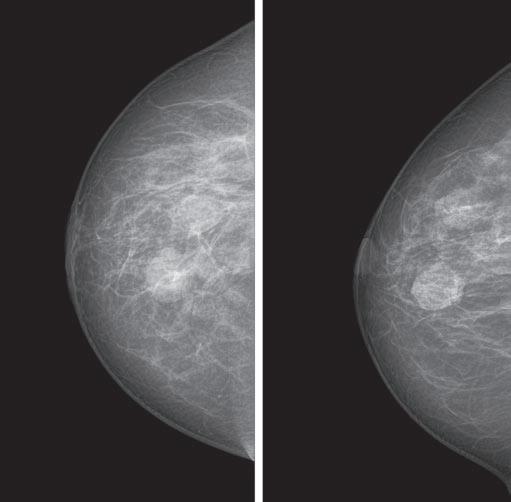

A yearly mammogram is the gold standard for breast cancer screening and detection. Mammography is the only test that has been scientifically proven to save lives. Still, it’s not infallible.

“In women with very dense breasts, mammography will miss cancer 58% of the time,” says Thomas Kolb, M.D., a breast cancer radiologist.

Dense breasts contain more glands, ducts, and connective tissue than fat. Breasts tend to be denser during a woman’s reproductive years. Density makes it harder to detect suspicious lumps on a mammogram; that’s because glandular tissue appears white on a mammogram, just like a mass can.

tomosynthesis, or 3D mammogram, takes images of breast tissue from multiple angles.

The latest in breast cancer detection technology, tomosynthesis, also known as 3D mammogram, is a digital mammogram that takes images of the breast in thin slices from multiple angles.

Tomosynthesis takes an arc of pictures through each breast, in 5-millimeter slices, which are then reconstructed into a three-dimensional image.

It allows radiologists to see through the breast tissue so they can more easily distinguish a true

mass from overlapping structures that can hide or mimic cancer, such as ligaments or glandular tissue.

Tomosynthesis can be used for screening and diagnostic mammograms.

Pros/cons: Compared to a digital (2D) mammogram, tomosynthesis is more precise. Studies show that three more women per thousand will receive a cancer diagnosis with tomosynthesis, compared to a digital mammogram.

Also, women with dense breasts who undergo tomosynthesis are 40% less likely to be called back for additional imaging.

Should you ask for it? Screening tomosynthesis is in order if you have dense breasts or you’re at average or intermediate risk for breast cancer.